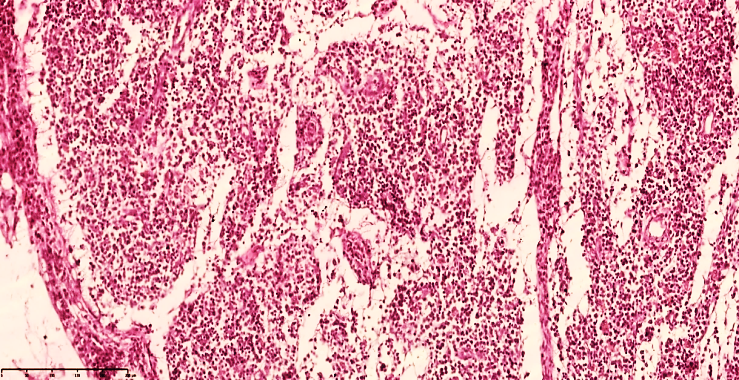

It was found that the main part of the regional lymph nodes is located in the ileocecal mandible and that massive enlargement of the lymph nodes occurs precisely in peritonitis. The lymph node capsule is tense, of uniform thickness, and reticulocytosis and macrophages are retained in the subcapsular space. As a result of the sharp increase in the level of fluid drainage, massively denuded stroma is detected in the lymphoid follicles in the active areas of the lymph node (cortical and paracortical areas) (see Figure 2). This indicates a connection with the massive recruitment of lymphocytes to the foci of inflammation. As a result, the lymph node acquires a swollen appearance, and loose lymph nodes are detected. The appearance of lymphoid follicles is sharply blurred against the general background, the follicle texture is lost, and neutrophils are detected around the postcapillary venules in the paracortical area. (see Figure 3). The abundance of mast cells confirms the acute course of the inflammatory process. | Figure 2. Mesenteric lymph node of a 28-day-old infant with peritonitis. The capsule is thickened, the subcapsular space is markedly enlarged, the peritrabecular areas are bare, formed in the form of a cavity, and the lymphoid follicles do not have a clear border. Staining G.E. Size 10x10 |